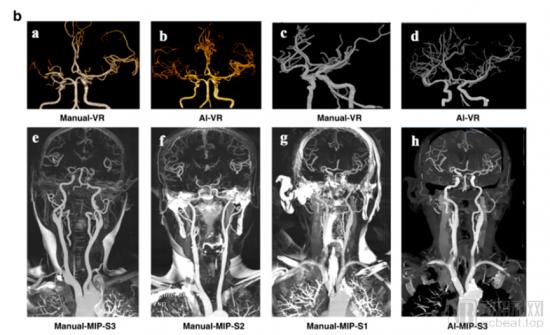

该论文主要提及的是一个颇有意思的系统:利用3D卷积神经网络设计了一个可实现头颈CTA血管分割的后处理系统,能够自动除去骨影像,并完成头颈CTA血管重建。

通俗来讲,该研究团队通过采集5家国内顶尖三甲医院18259例头颈CTA数据,经过两年的神经网络系统的深度学习,已经可以实现在只需要一次CT扫描的情况下,患者便能获得可用于重建的影像(CTA)结果, 且在论文发布时,AI的重建准确率已经趋近于100%,与资深医师相当。

该AI模型重建VR图像血管边界更光滑、去骨效果更佳。

卢洁教授团队与数坤科技重塑了脑血管CTA检查行业的运作方式,AI终于可以以更高效率、更高诊断精准度介入到脑部CTA检查之中。在此之前,在心脏AI影像领域,头部企业数坤科技已经率先在“数字心”的关键领域“血管分割技术”方面取得了突破,相关AI技术和设备已经在多家三甲医院落地。